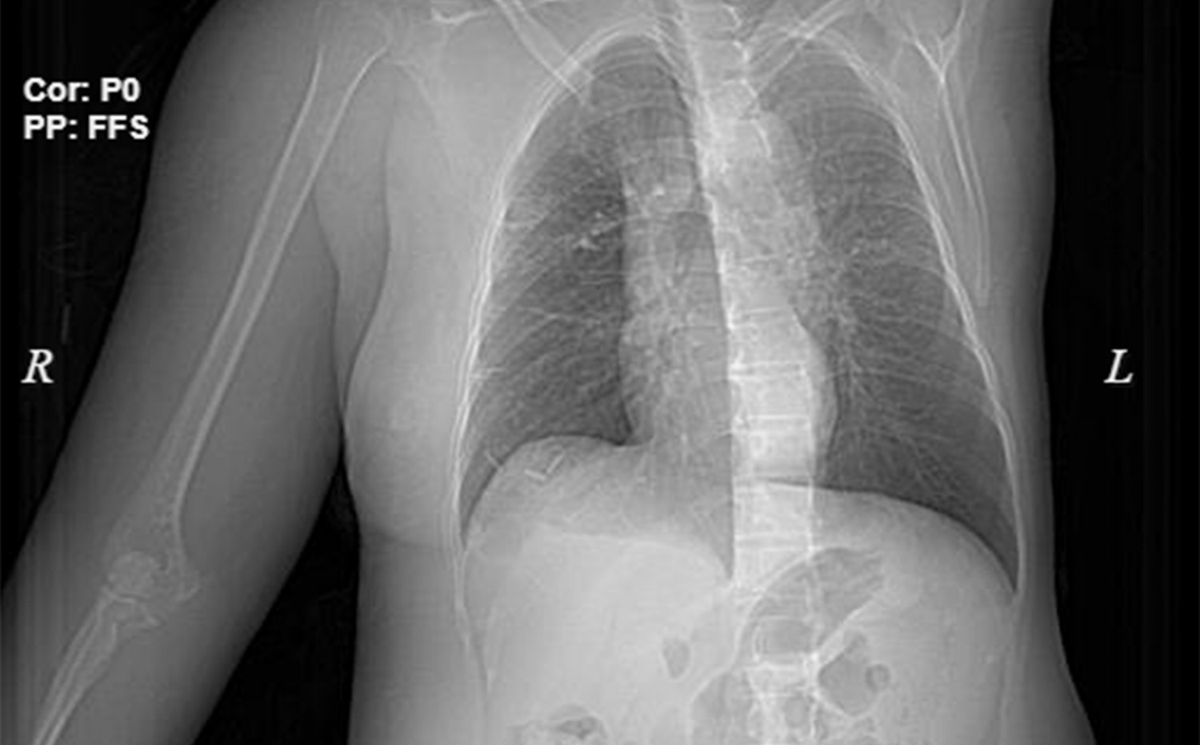

Hình ảnh phim chụp ngực phải của bệnh nhân sưng to do điều trị ung thư vú sai cách.

Theo BS Hứa Văn Đức - Trưởng khoa Ung bướu, Bệnh viện Đa khoa Hùng Vương, sau khi thăm khám và làm các xét nghiệm, bệnh nhân được chẩn đoán ung thư vú giai đoạn cuối, khối u di căn hạch nách và xương cánh tay phải, vùng đắp thuốc nam bị nhiễm trùng có nguy cơ hoại tử, nhiễm khuẩn huyết.